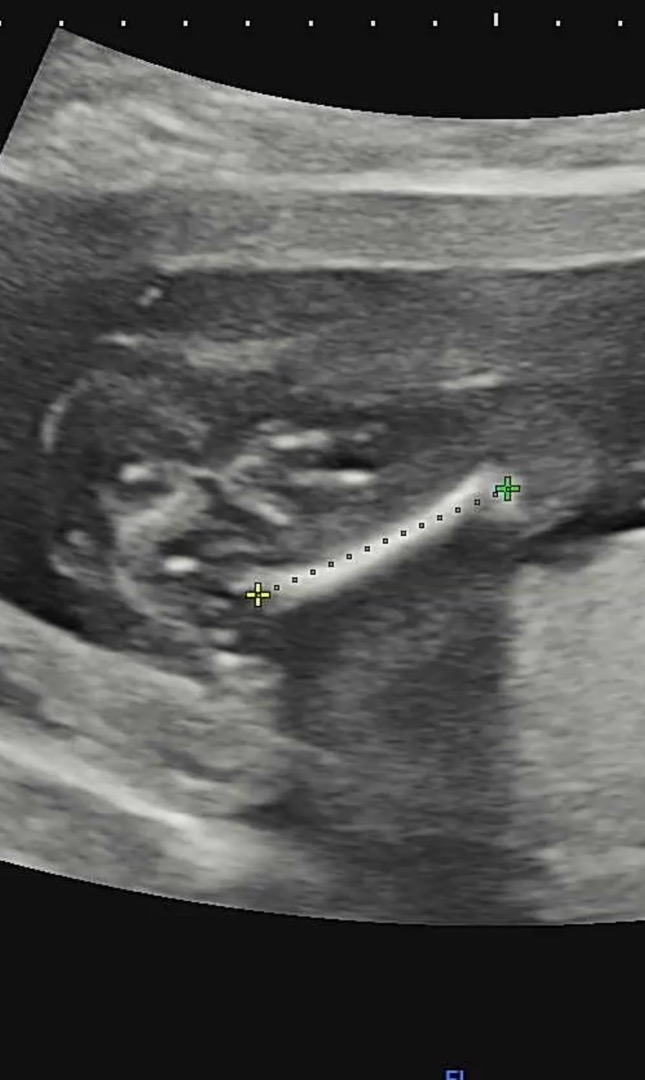

16주 0일 초음파인데..

딸일까유..? 오늘 초코우유도 먹고 초음파 보러 다녀왔는데 애기가 안보여준다고 근데 선생님께서는 공주님같다구 하셨거든요.. 그동안 심소랑 태몽이랑 땡기는 음식으로 아들이라고 생각하고 살았는데..정말 딸일까요..?🤍🌝

엉덩이와 다리사이에 뽀족한게 없음 딸이예요

그쵸..근데 다리 딱붙이고있을땐 안보이다가 다리 벌리니까 아들이었다고하는 분들도 많아서요..딸이든 아들이든 기다리던 아기라 상관없눈데 육아용품 사거싶어서 궁금해유..힝 ㅜㅜ